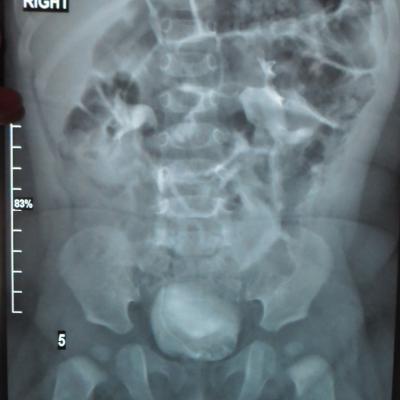

Моему ребенку 1 год 1 месяц. Во время беременности у плода было обнаружено увеличение лоханки слева - 9мм. Далее по результатам УЗИ после рождения максимальное увеличение достигало 17 мм. В 5 месяцев проходили урологическое обследование, результаты цистографии: мочевой пузырь округлой формы. Контуры ровные. ПМР нет. ЭЭД-1,2МЗВ; урографии: рентгеноконтрастных теней конкремента нет, почки в типичном месте, размеры сохранены, структура ЧЛК справа не изменена, слева пиелоэктазия, подвижность допустима, функция сохранена, ЭЭД – 0,4 МЗВ. По последнему УЗИ (1 год) увеличение лоханки слева - 28 мм. Мочеточники и сама почка в норме. Результаты анализов мочи за этот год хорошие (сдавали ежемесячно). В чем могут быть причины данного явления и чем это грозит малышу?

Ответ врача

В данном случае - сужение лоханочно-мочеточникового сегмента и\или добавочный сосуд(слева). Но выделительная функция почки сохранена. В данный момент целесообразно наблюдение, но в дальнейшем - не исключено хирургическое вмешательство.